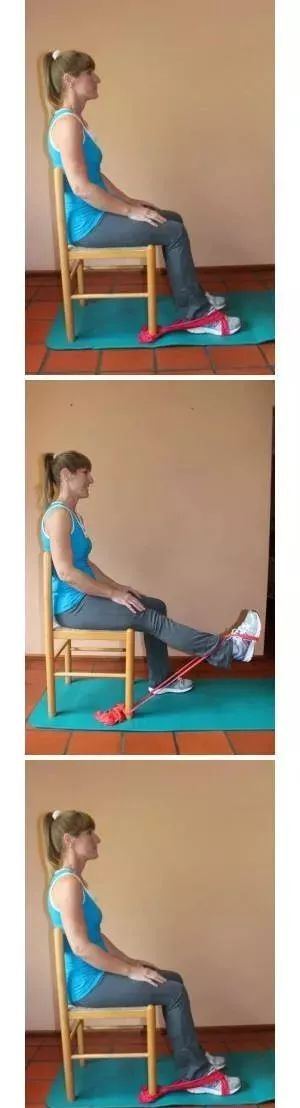

五

脚踝和沙袋负重练习

沙袋可以增加股四头肌的压力,可以在上述每个练习中添加沙袋来增加力量。

六

脚踝和力量带辅助练习

”